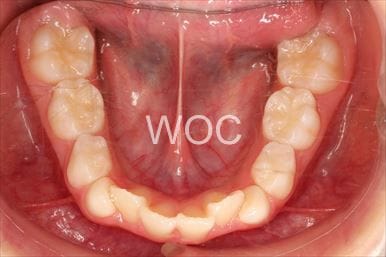

治療後1

- 年齢:20歳女性

- 主訴:出っ歯が気になる

- 基本矯正料金:120万円

- 治療期間:1年7ヶ月

- 抜歯部位:上顎両側第一小臼歯